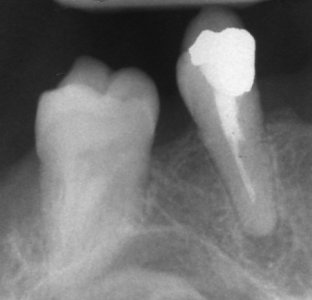

Ендодонтия